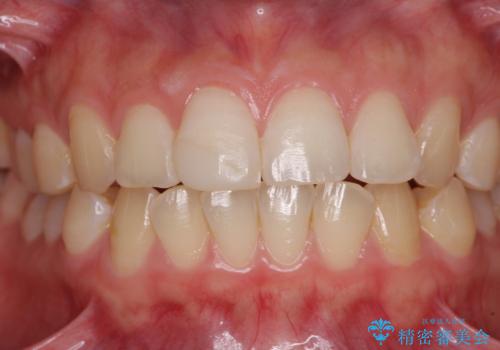

転倒して欠けてしまった前歯をオールセラミッククラウンで自然な口元に

転倒などの強い力がかかった歯は、歯の内部の歯髄組織が壊死してしまったり、外部吸収と知って、歯根の一部が吸収してしまったりと、思わぬ問題を抱えていることがあります。

治療期間においてはこのようなトラブルは発生していませんでしたが、今後も定期的にレントゲン写真撮影などで経過を見ていく必要があります。